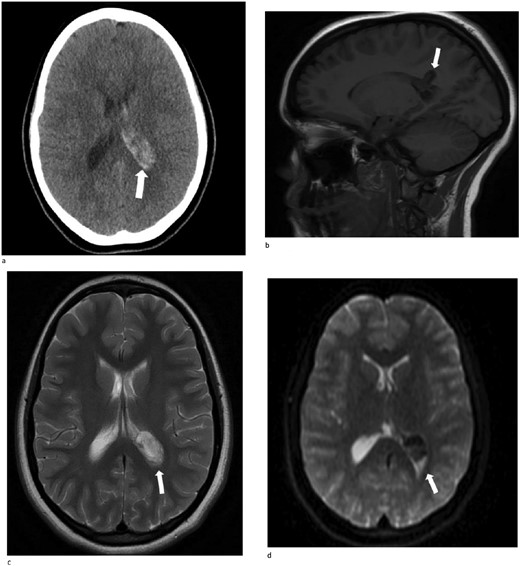

A 13-year-old female presented with an abrupt onset of a severe headache accompanied by two episodes of vomiting, left-sided jaw pain, nausea, and nasal congestion. She did not report any numbness, tingling, muscle weakness, or changes in vision. An initial non-contrast CT scan of the head revealed a left lateral intraventricular hemorrhage, (Fig. 1a). There were no intraparenchymal hemorrhages, midline shifts, or extra-axial fluid accumulations. MRI revealed a hemorrhagic lesion measuring 2.1 cm × 1.6 cm × 2.6 cm, involving the left atrium and the adjacent periventricular deep white matter (Fig. 1b). There was thickening of the choroid plexus, with no significant vasogenic edema or acute extra-axial fluid collection, and no signs of brain herniation.

(a)–(d) Demonstrates evidence of a hemorrhagic lesion involving the left atrium and adjacent periventricular deep white matter with a moderate amount of intraventricular hemorrhage within the left ventricle.